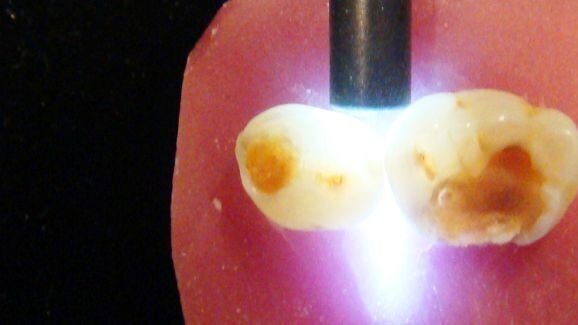

RIBEIRÃO PRETO/SP- Pesquisas são feitas na Faculdade de Odontologia de Ribeirão Preto (FORP) com a utilização de laser para a prevenção de cárie radicular (na raiz dos dentes). A técnica experimentada permite prevenir a cárie com mínima intervenção, como acontece atualmente com a aplicação de flúor. O método pode evitar a necessidade da realização de tratamento restaurador nos dentes.

O estudo teve como objetivo avaliar em laboratório a eficácia da irradiação de lasers no tratamento de prevenção de cárie radicular, analisando a influência do tipo de laser empregado associado ou não ao flúor, sendo que atualmente o tratamento é feito com broca e restauração com material normalmente estético.